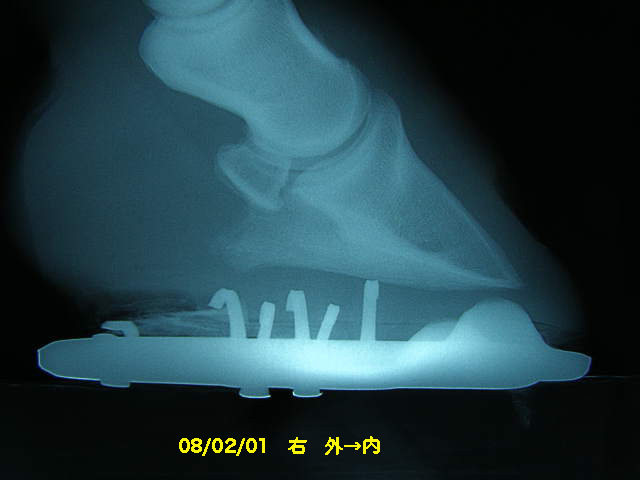

9月の右前肢

今回の右前肢

こちらも蟻洞がなくなりました。

ヒールアップに関して、蹄壁と蹄底の角度を測ってくれました。

前回は65°。

パットをフラットなものにしたら62°。

3°の変化でも本人にとっては大きく変化したようで、だいぶ軽快に肢を運ぶようになりました。

見た目的にも前回の装蹄後よりも蹄の傾きが緩やかになり、私もホッとしました。

次回からは削蹄で少しずつ角度を寝かせていくそうです。